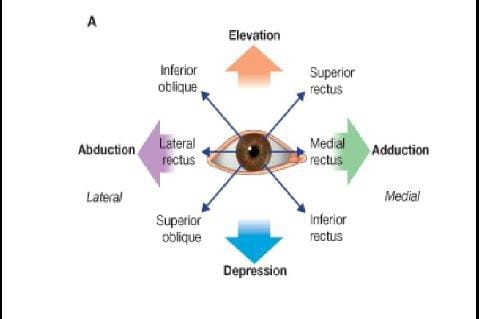

Extraocular Muscle Actions: Eye Movements, Rectus Muscles, Oblique

www.pinterest.com

www.pinterest.com

oblique rectus movements extraocular movement nerve adduction abduction tms ocular temporal trochlear depression

Muscles Of Eye - Ophthalmology - Medbullets Step 2/3

step2.medbullets.com

step2.medbullets.com

oblique rectus muscles inferior superior eye movement medial nerve ophthalmology medbullets topic

Muscles Of Eye - Ophthalmology - Medbullets Step 2/3

step2.medbullets.com

step2.medbullets.com

eye muscles movement ophthalmology medbullets topic

Eye muscles extraocular actions ocular control motor synergistic right their pull antagonistic directions direction medical same section anatomy. Lateral eye movement although a horizontal, frontal dipole is the key. Extraocular muscle actions: eye movements, rectus muscles, oblique